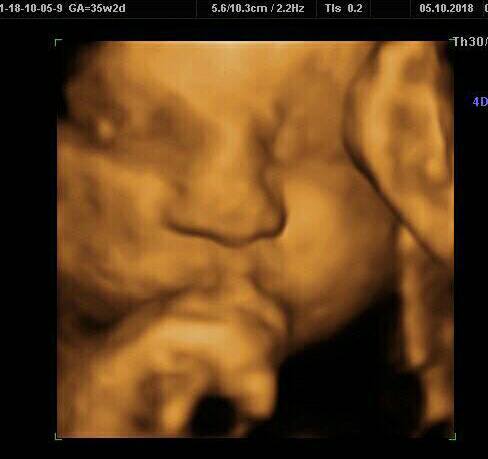

Mati dziś ładnie współpracował, choć był odwrócony do nas tyłem.

Udało się popatrzyć na jego buzię.

Ma ok 40cm i 1785g. No i rączki cały czas przy buzi

Słodziak [emoji7][emoji8]